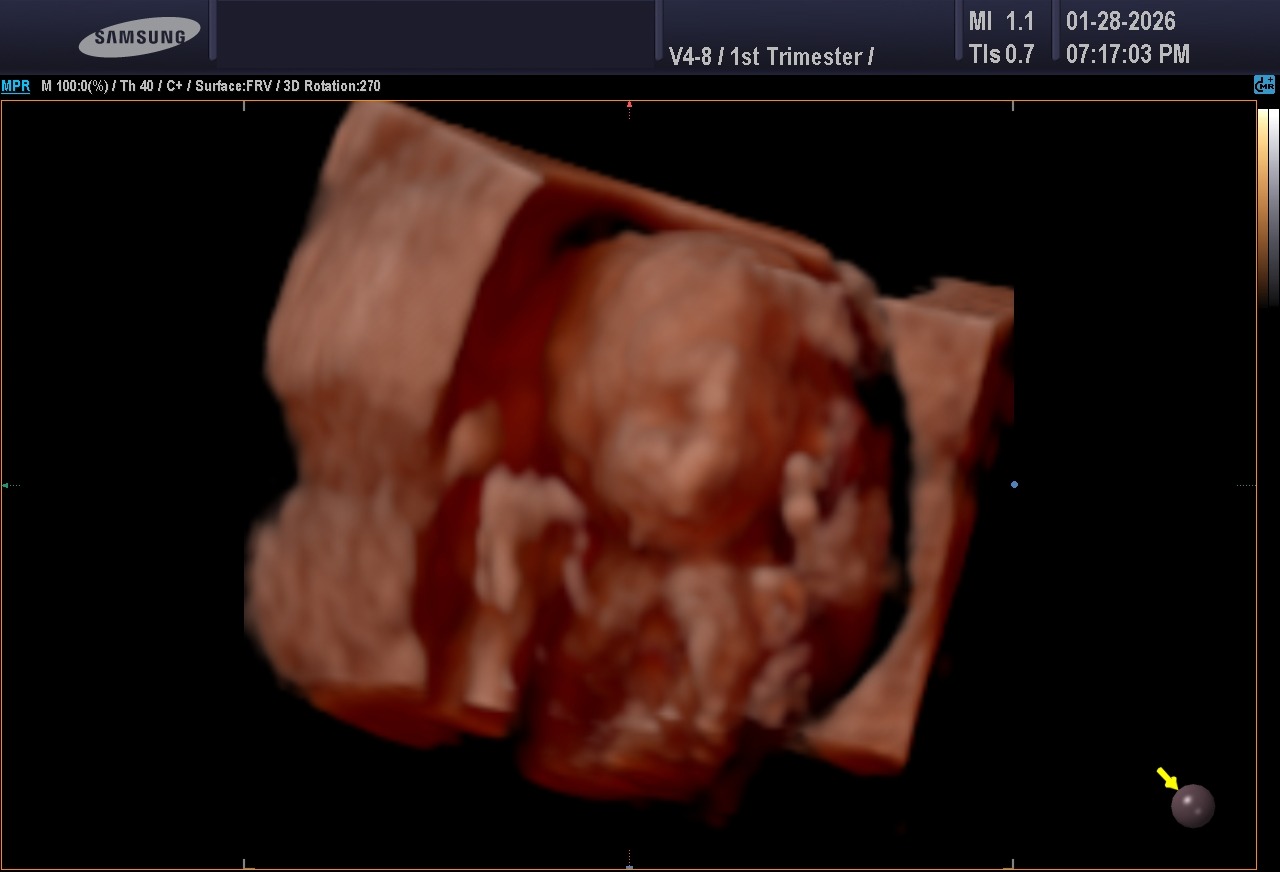

Hello, everyone. My name is Lala. My husband's name is Brian. Unfortunately, I had to come here and ask for help from family members, friends, and anybody who maybe has gone through this and knows how tough it can be. But just at twenty-two weeks and four days, on Monday night, my water broke and I went into labor. I delivered my baby boy, Brian Jr., on March 17th. Tragically, he was only able to spend eleven minutes with us before passing away in his father's arms. The overwhelming loss of our baby boy has brought unimaginable pain and grief, and Brian and I are left to lean on one another as we try to navigate this overwhelming loss.